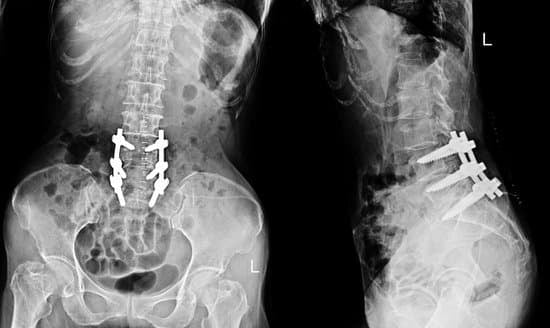

척추 사이에 뼈 이식물(자체 뼈 또는 인공 이식물)을 삽입하고, 나사와 금속 막대를 이용하여 척추뼈를 고정합니다.

이 이식물이 시간이 지나면서 주변 뼈와 융합되어 하나의 단단한 뼈 구조를 형성합니다.

정기적인 검진: 뼈의 융합 상태를 확인하기 위해 정기적인 진료와 X선 촬영이 필요합니다.